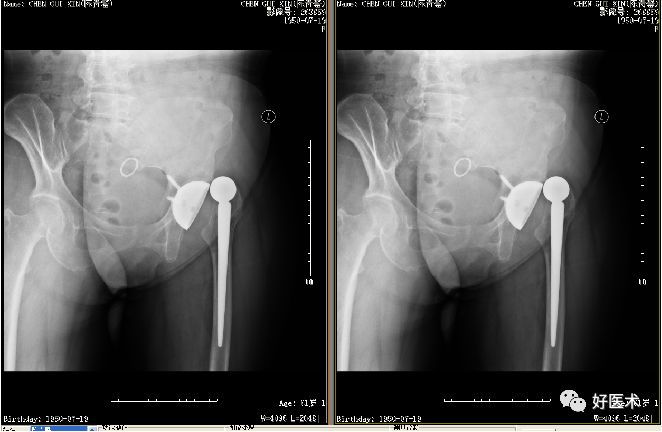

一、脱位

最常见的并发症之一:

-

初次THA术后的脱位率为0.2%~7%

全髋翻修术后的脱位率为10%~25%

原因

术式

如前侧切口易发生前脱位,

后侧切口易发生后脱位,可高达5.8%,是前侧和外侧切口入路的2倍,

外侧和前侧入路脱位率分别为3.1%、2.3%。

假体位置是否放置准确,

正确的假体髋臼角应在45°左右,

前倾角15~20°左右。

角度太大易发生脱位。人工股骨头皮缘与髋臼缘边缘平行-理想的位置。

处理

早期脱位应尽早复位,

X线表明假体位置合适的病人应争取麻醉下手法复位,其成功率为63%~83%,复位后必须经X线证实并用皮肤牵引或“丁”字鞋固定3~6周。

除假体位置不良外,脱位超过数小时,组织肿胀,肌张力较高,手法复位多次均失败或复位后易复发的病例均应作手术治疗。

X线位置好,可先作小切口,用手指探查并协助牵引复位。

X线证实假体位置不良,尽早原切口复位。